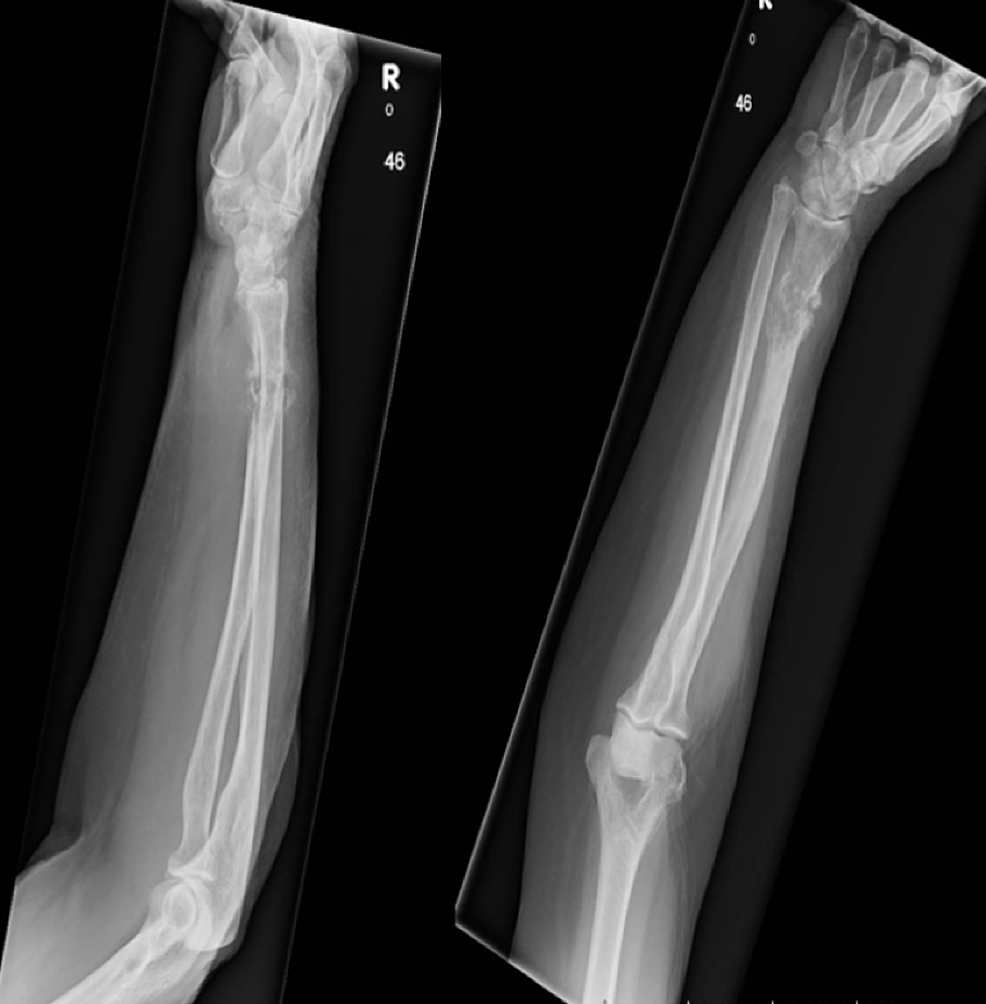

From buyxraysonline.com

BONE CANCER Melanoma Bone Cancer — when a lesion of malignant melanoma is encountered within bone, two possibilities are considered for its origin:. — metastatic bone disease (mbd) carries significant morbidity for patients with cancer. — in this narrative review, we describe the management of patients affected by melanoma bone metastases,. bone is the fourth most common site of melanoma metastasis. Melanoma Bone Cancer.